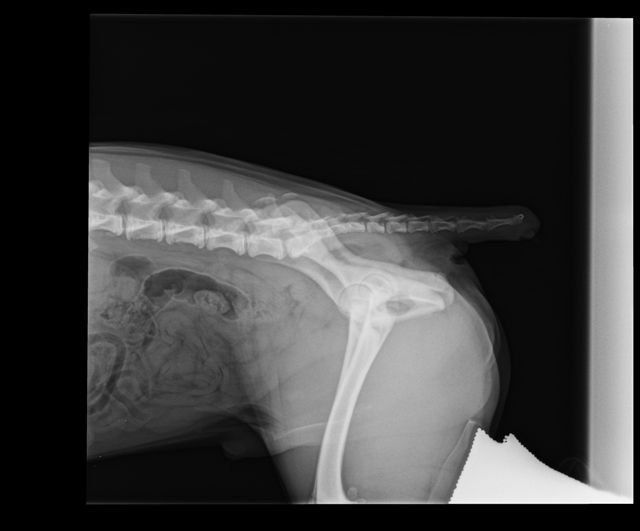

Presso la nostra clinica, la prevenzione della displasia delle anche inizia con uno studio radiografico approfondito, effettuato in anestesia o sedazione controllata. L’esame è sicuro e permette di valutare l’articolazione anche nei cuccioli, già a partire dai 3 mesi e mezzo di età.

L’indagine comprende:

- visita clinica ortopedica completa;

- radiografie in più proiezioni (standard, distratta, a rana e DAR);

- valutazione della colonna e, se necessario, anche dei gomiti.